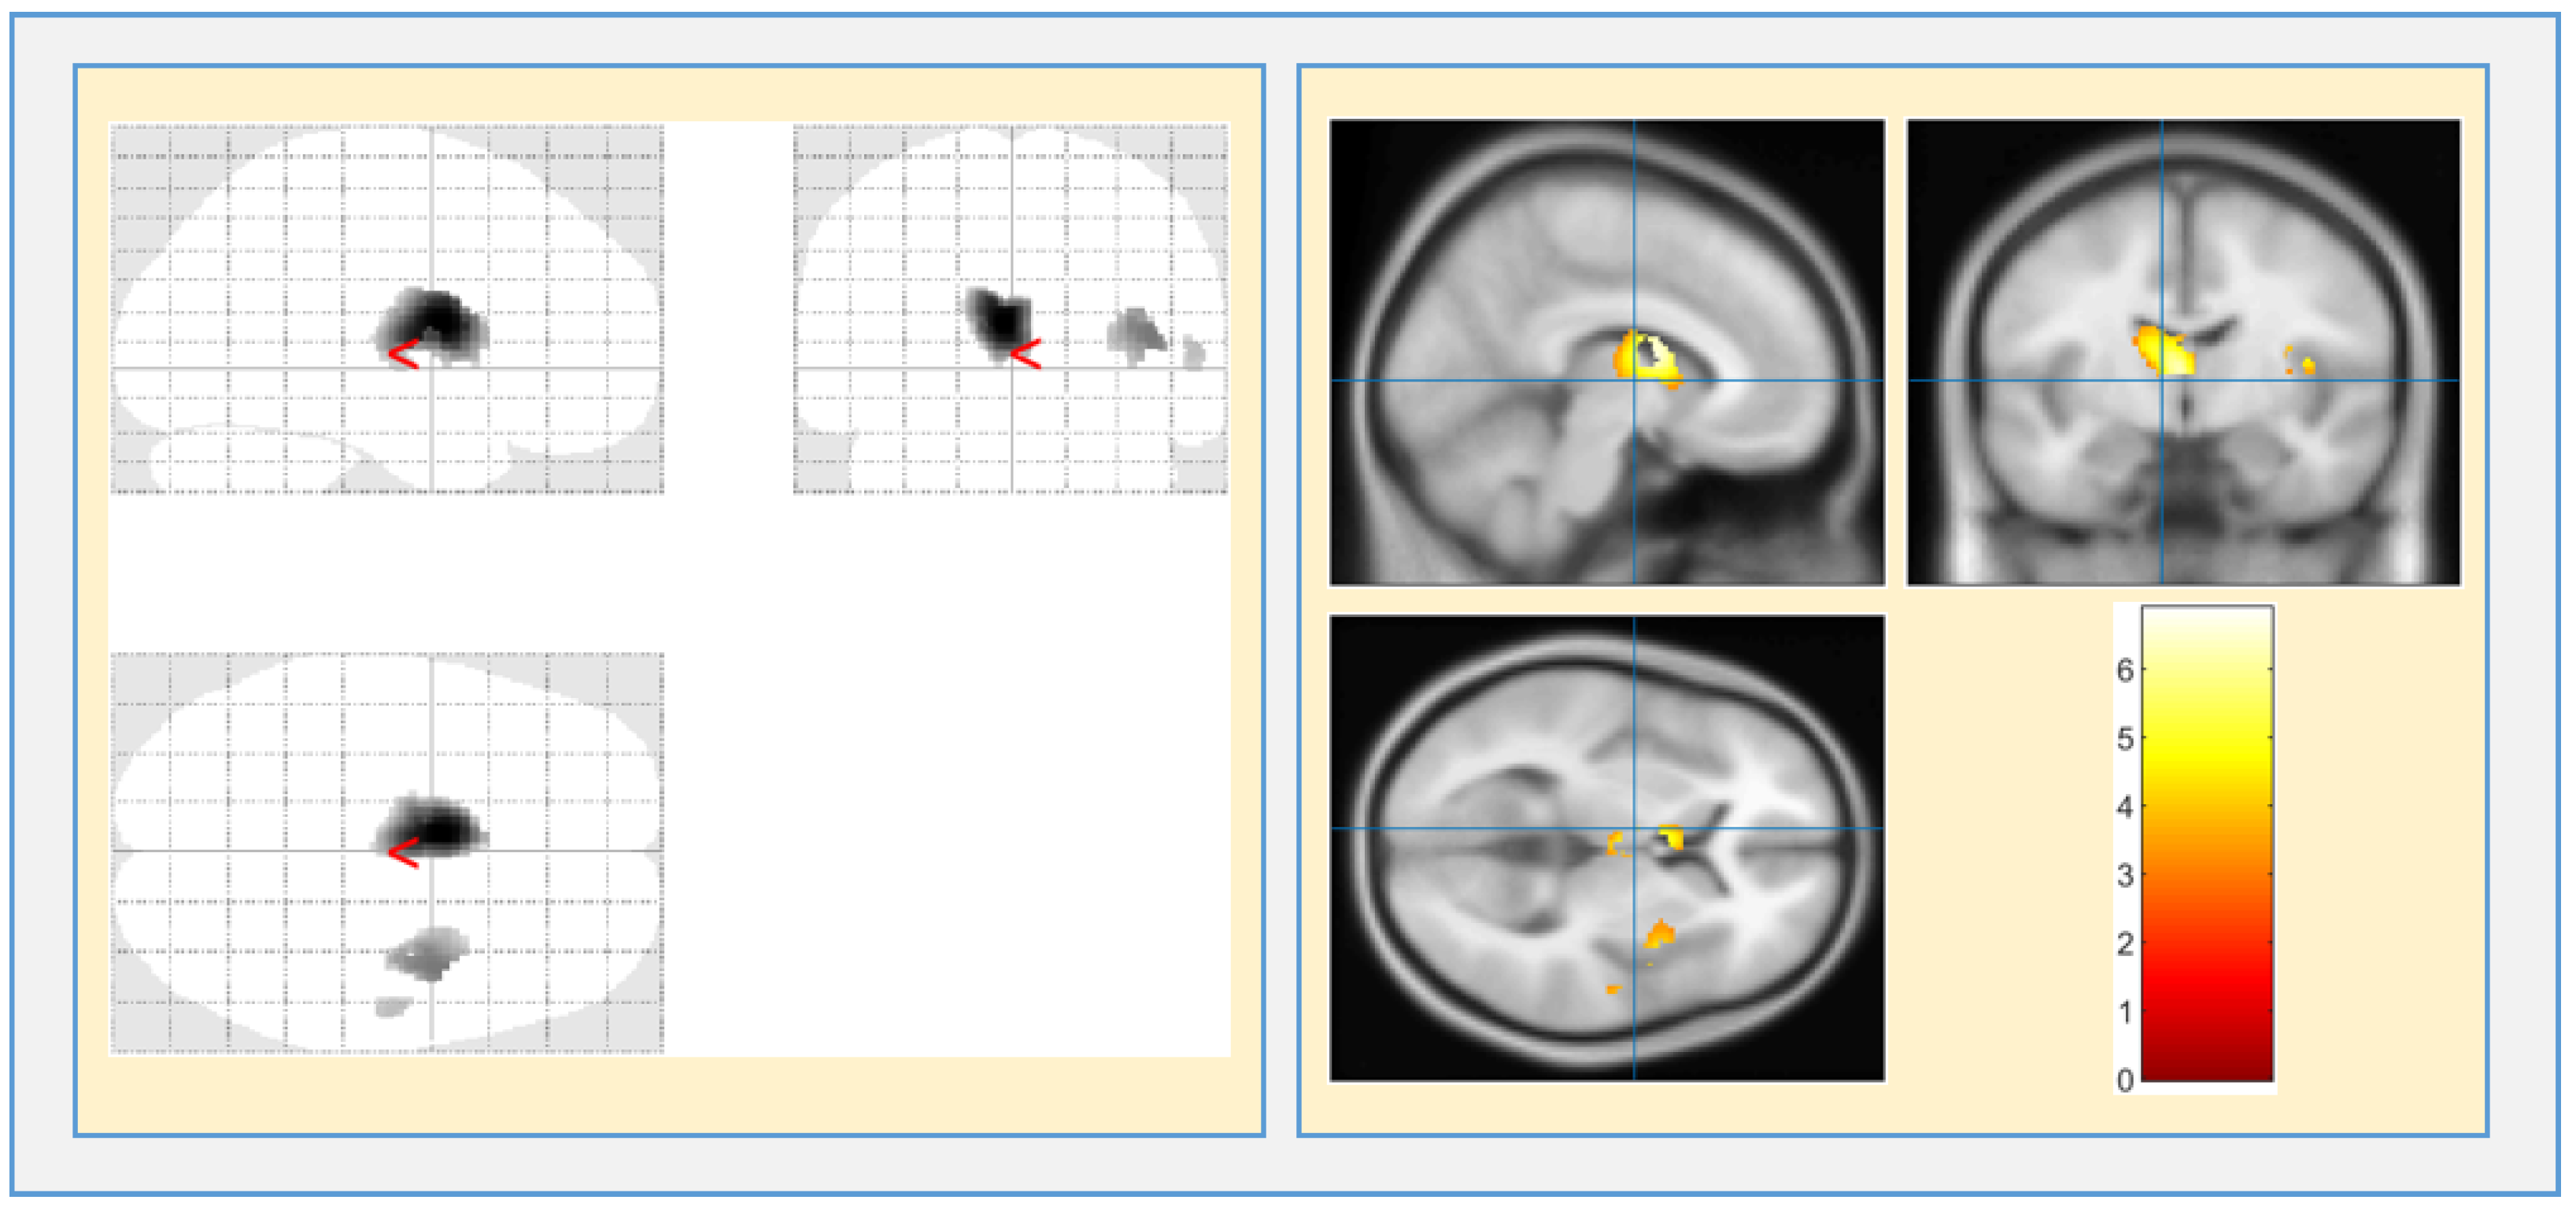

| Region of Interest | Anatomical Region | Voxels | T-Value | Z-Value |

|---|---|---|---|---|

| WM | Left cerebrum Internal Ventricle | 1363 | 6.90 | 6.21 |

| Right cerebrum Insula | 340 | 4.83 | 4.56 | |

| Right cerebrum Temporal lobe | 41 | 3.70 | 3.57 | |

| GM | Left cerebrum Extra -Nuclear | 12 | 4.82 | 4.56 |

| Right cerebrum Temporal lobe | 27 | 4.64 | 4.40 | |

| Left cerebrum claustrum | 6 | 3.47 | 3.36 | |

| CSF | No Clusters are identified | |||